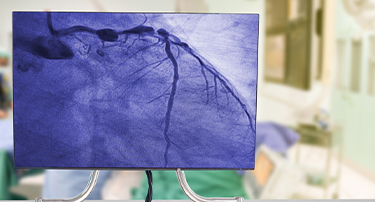

A Complete Guide to Heart Bypass Surgery: Why It’s Done, How It Works & What to Expect

Heart bypass surgery, or coronary artery bypass grafting (CABG), is a life-saving surgery that is done to enhance the flow of blood to the heart when the coronary arteries are blocked or narrowed very much. Such a condition, or coronary artery disease (CAD), may result in chest pain (angina), shortness of breath, and a higher risk of heart attacks.

Heart Bypass Surgery: Purpose, Procedure, Risks And Recovery

Heart bypass surgery, also called CABG, is a critical surgical procedure used to ensure adequate blood flow to the heart when the coronary arteries have blockages or are narrowed with coronary artery disease (CAD). Blockages in the coronary arteries reduce the oxygen supply to the heart. This can result in chest pain and shortness of breath, and may even lead to heart attacks, which can be fatal. This surgical procedure is often recommended when lifestyle modification, drugs, or other minimally invasive treatments do not respond to the condition.

What Is The Purpose Of A Right Heart Catheterization?

Right heart catheterization is another intervention that entails the use of a catheter to take measurements regarding the functioning state of your heart. This is done by passing a thin and flexible tube called a catheter through a vein in your neck, groin, or arm then threading it to your heart. This procedure enables the doctor to estimate the strength with which the heart is pumping blood and measure the pressure of blood in the heart, and the level of oxygen.